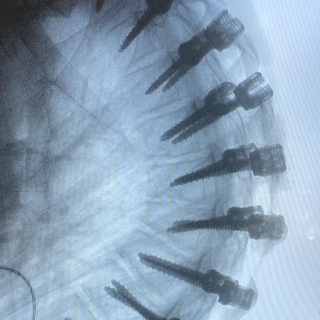

На сагиттальной рентгенограмме женщины, 45 лет: смещен 5 поясничный позвонок кпереди относительно крестца, здесь показана хирургическая фиксация винтами со стержнями и межпозвонковым кейджем.

«Спондилолистез – переднее, заднее или боковое соскальзывание или смещение позвонка относительно нижележащего – можно объяснить элементами дисплазии соединительной ткани. Первое описание спондилолистеза приписывают Herbinaux – бельгийскому акушеру, который отметил костную выпуклость, препятствовавшую родоразрешению. Термин «спондилолистез» был введен Kilian в 1854 г. от spondylos (греч. «позвонок») и olysthesis (греч. «соскальзывание»). Спондилолистез часто формируется на уровне поясничных позвонков, что обусловлено большей статической нагрузкой на них, слабым связочным аппаратом, большой высотой диска, сагиттальной ориентацией суставных поверхностей дугоотростчатых суставов.»

Хитров Н. А. «Возрастные аспекты дорсопатий»